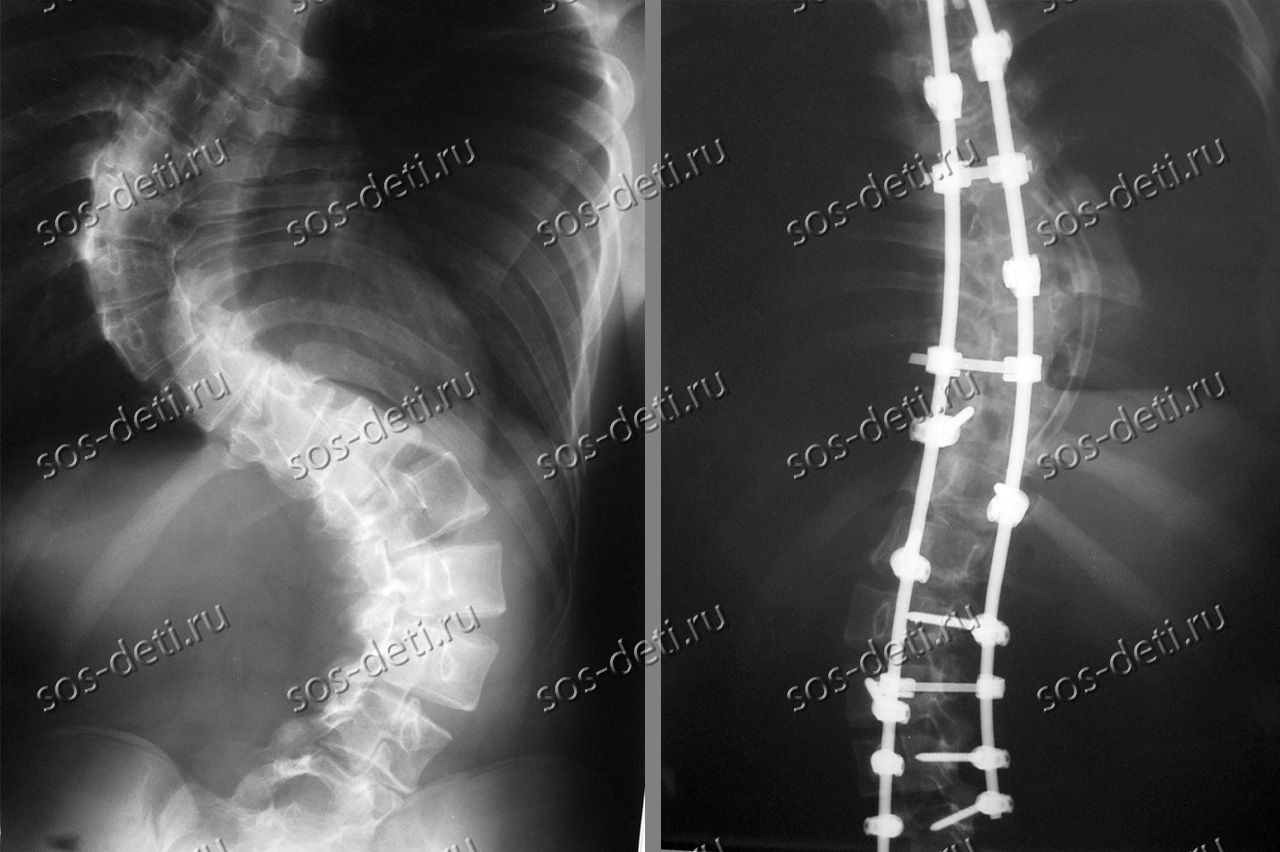

Татьяне 14 лет, она из Калуги. Её диагноз – идиопатический левосторонний поясничный сколиоз 4 степени. Впервые сколиоз выявлен в 7 лет при медосмотре перед школой. Последние два года наблюдается резкое прогрессирование до 85 градусов, начал расти горб, усилились боли в спине и ногах. Избежать неврологических осложнений и устранить искривление поможет операция коррекции деформации позвоночника современной металлоконструкцией. Оплата имплантатов за счет бюджетных средств не производится. Стоимость базовой комплектации имплантатов и расходных материалов составляет 721 100 рублей.

Главный врач Калужской областной детской больницы В.М.Михайлов обратился с просьбой о помощи в обеспечении операции по установке имплантатов стабилизации позвоночникаMedtronic (США). Стоимость проведения операции, необходимого медикаментозного обеспечения и последующей реабилитации оплачивается за счет бюджетных средств. К сожалению, бюджетом не оплачивается стоимость имплантатов, поэтому Татьяна будет прооперирована только при условии привлечения необходимых благотворительных пожертвований.